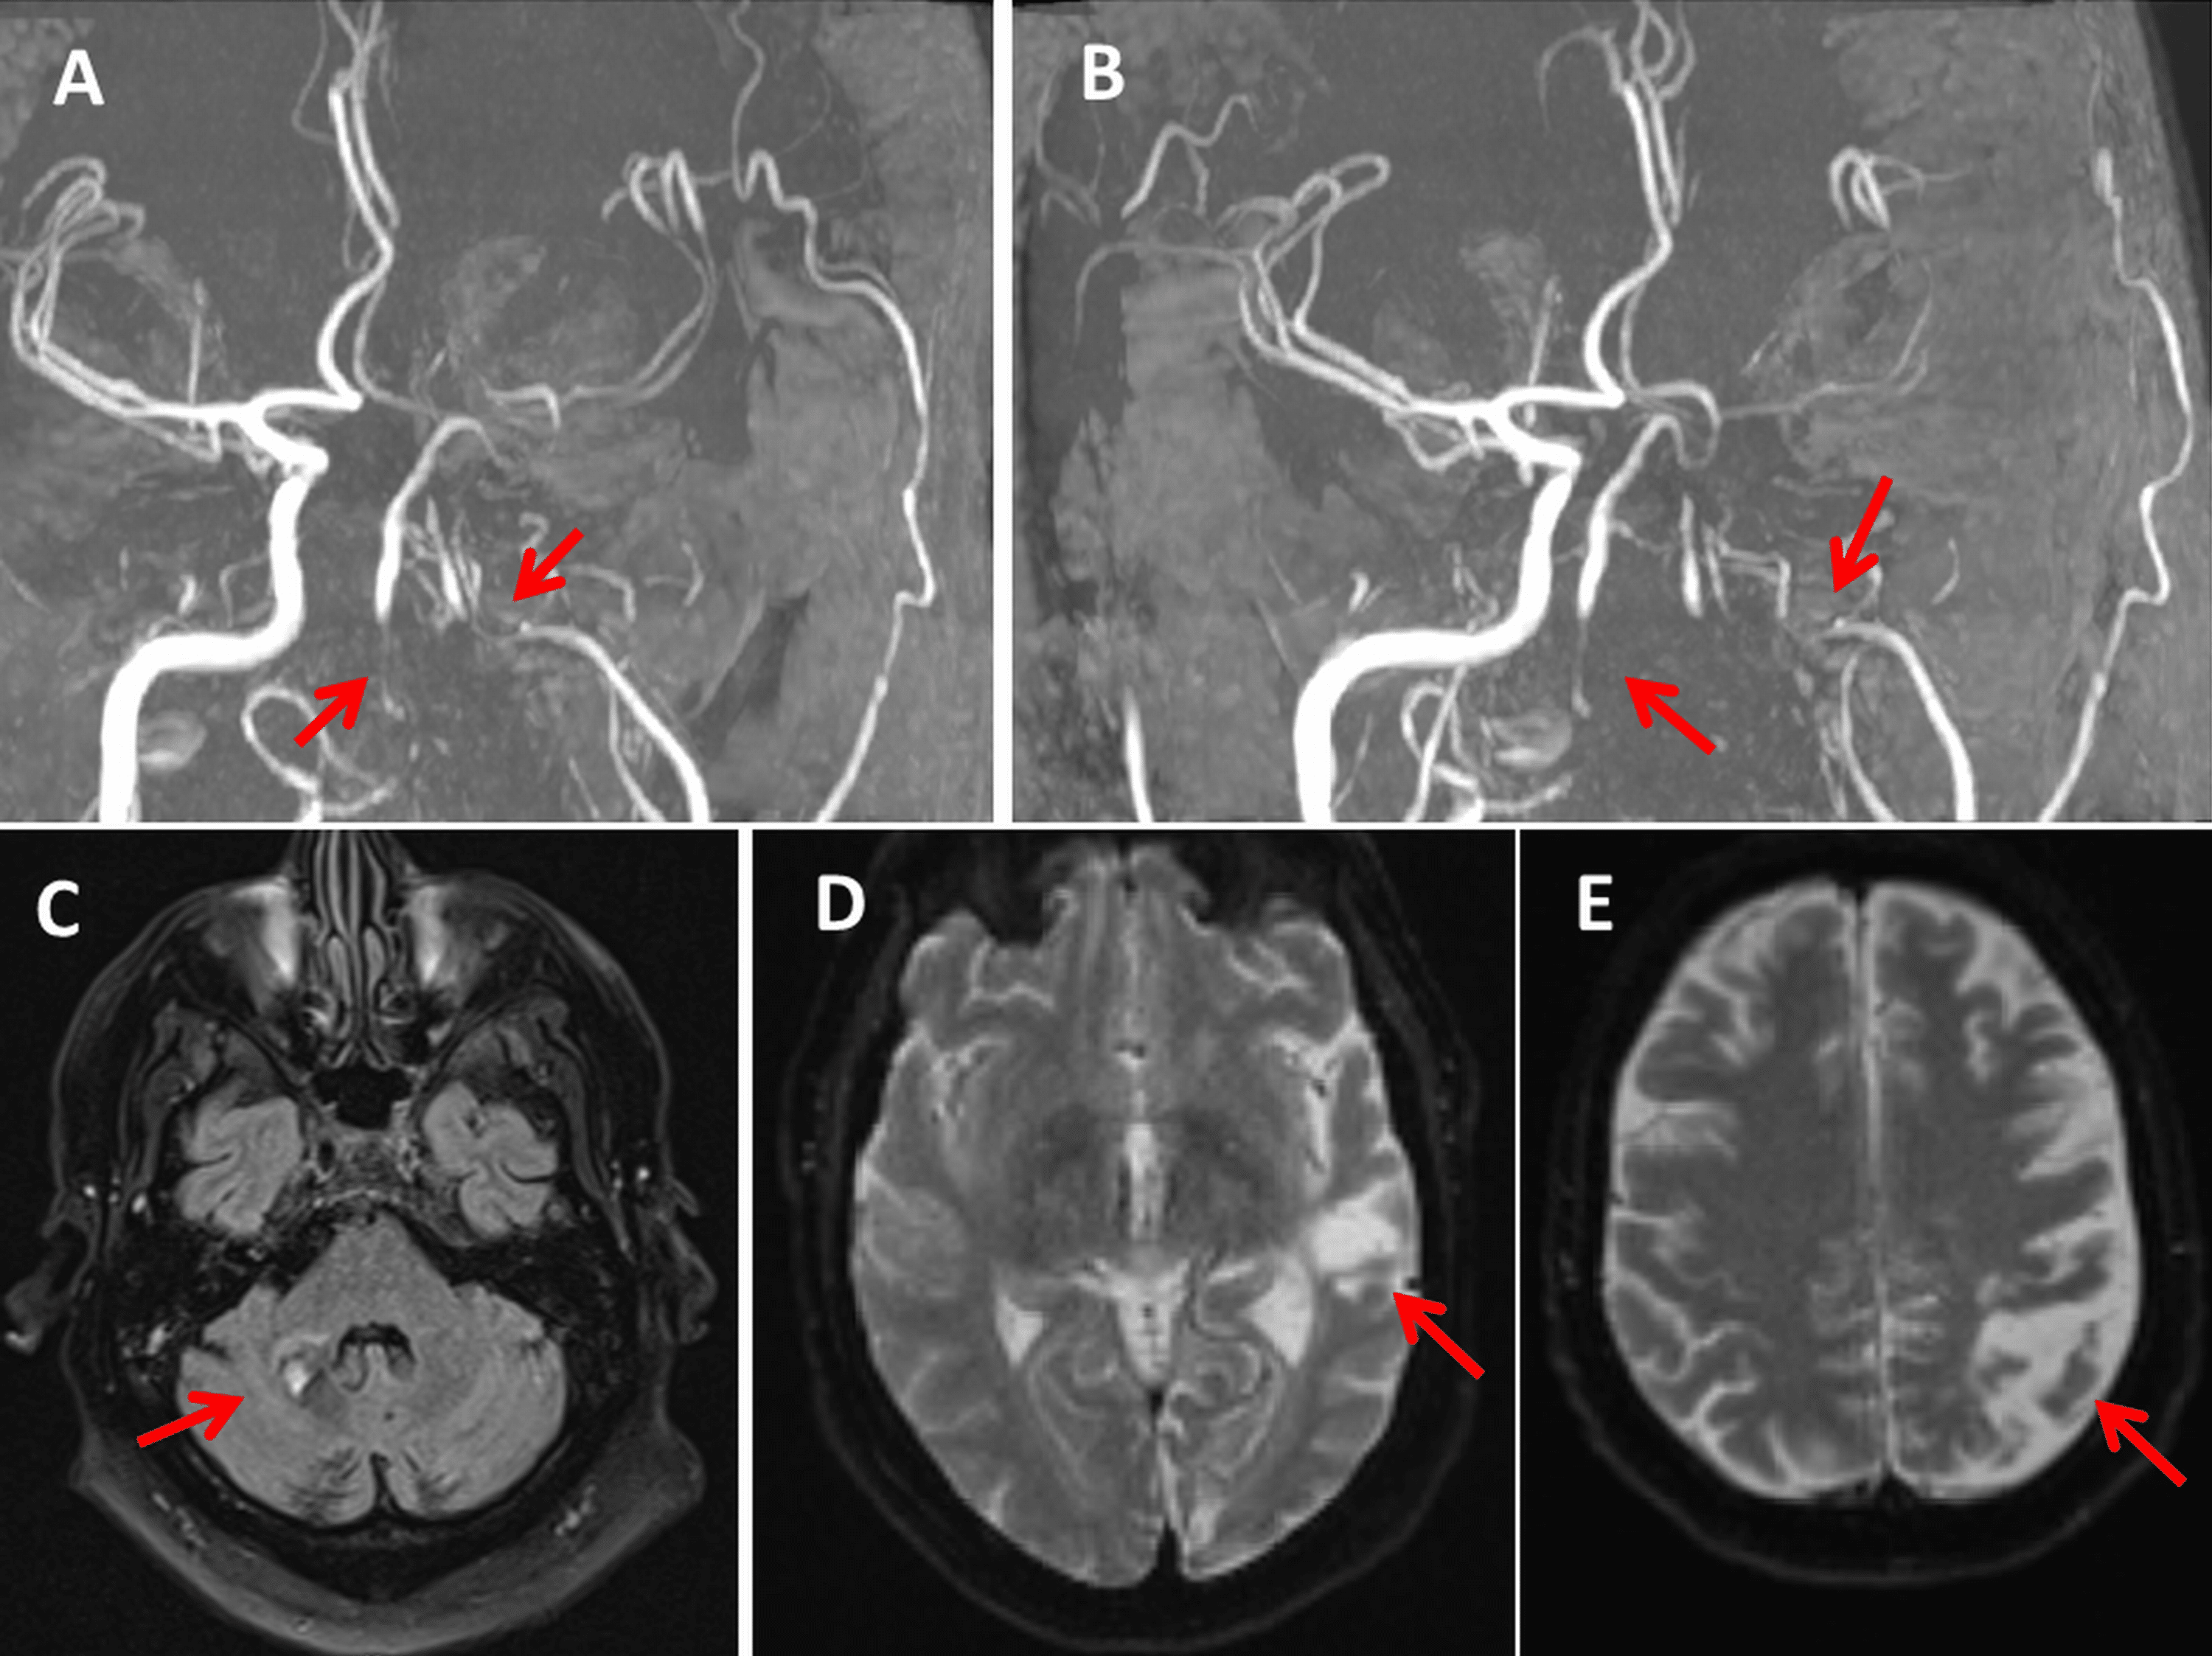

From www.cureus.com

Hereditary Protein S Deficiency and Activated Protein C Resistance Protein S Deficiency And Epidural For women with a family history of vte who have protein c or protein s deficiency, the ash guideline panel suggests postpartum. Protein s deficiency is an inherited thrombophilia associated with an increased risk of thromboembolism. A deficiency in protein s characteristically demonstrates the inability to control coagulation, resulting in the excessive. Recently, gris and colleagues reported that treatment with. Protein S Deficiency And Epidural.

Hereditary Protein S Deficiency and Activated Protein C Resistance Protein S Deficiency And Epidural For women with a family history of vte who have protein c or protein s deficiency, the ash guideline panel suggests postpartum. A deficiency in protein s characteristically demonstrates the inability to control coagulation, resulting in the excessive. Recently, gris and colleagues reported that treatment with 40 mg enoxaparin daily in pregnant women with a thrombophilia. In summary, the successful. Protein S Deficiency And Epidural.

From www.semanticscholar.org

Figure 1 from Hereditary Protein S Deficiency and Activated Protein C Protein S Deficiency And Epidural In summary, the successful anesthetic management of a patient with protein s deficiency and ischemic heart disease is described. Recently, gris and colleagues reported that treatment with 40 mg enoxaparin daily in pregnant women with a thrombophilia. A deficiency in protein s characteristically demonstrates the inability to control coagulation, resulting in the excessive. For women with a family history of. Protein S Deficiency And Epidural.